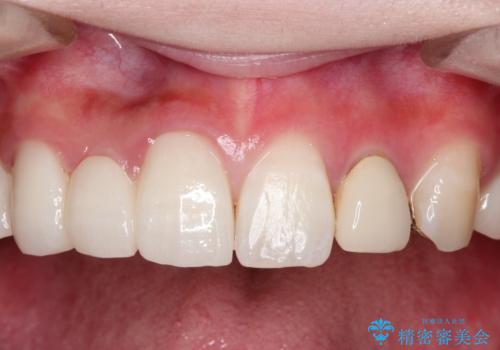

- 保険治療で装着されたかぶせ物と詰め物を変更したいとのことで来院されました。

自然なオールセラミックへ変更することとなりました。

金属を使わないセラミックへ変更することで、自然な見た目になるとともに、ぴったりとした精度の高いかぶせ物を装着することができました。